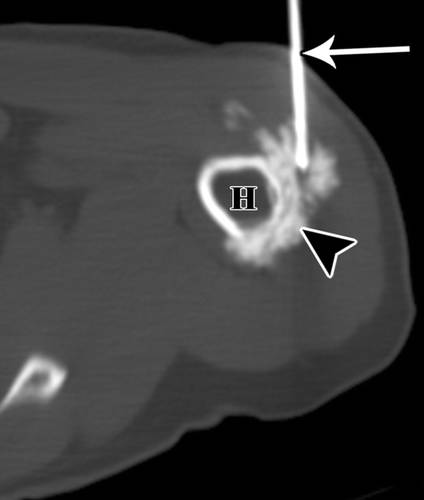

应避免穿过股直肌的前路(图9))。这些伸肌的切除(特别是股直肌)在保留肢体的手术中提供了不理想的结果。如果病变与股血管密切相连,则采用内侧入路是因为内侧切口有利于血管的探查。外侧入路通常更符合人体工程学的可行性,避免了内侧神经血管结构,尤其是如果股外侧肌无血管受累时(图10A,10B)。在大腿远端,髌上凹陷可能向近端延伸一个不同的距离,应该与其余的膝关节一起避免。对于内侧入路,我们可以提升腿部进行活检或弯曲,从外侧旋转对侧髋关节,以便于进入大腿内侧。

10A - 58岁男性转移性腺癌MRI冠状位。

10B - 58岁男性转移性腺癌CT引导下穿刺。